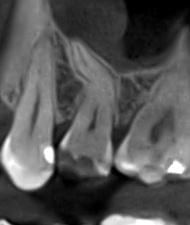

Коли коріння «ховає сюрпризи» - Корені зубів часто мають складну кривизну, гачкоподібні закручення або розгалуження, які на звичайному 2D-знімку накладаються один на одного, створюючи ілюзію прямого каналу. На плоскій картинці неможливо побачити реальний об'єм та напрямок вигину, що критично важливо при видаленні «зубів мудрості» або ендодонтичному лікуванні. КТ MyRay дає змогу лікарю заздалегідь побачити 3D-геометрію кожного кореня, оцінити його близькість до нижньощелепного нерва чи гайморової пазухи та підібрати правильну тактику роботи. Це мінімізує ризики поломки інструменту в каналі або травмування сусідніх структур, перетворюючи складну хірургію на прогнозовану процедуру.